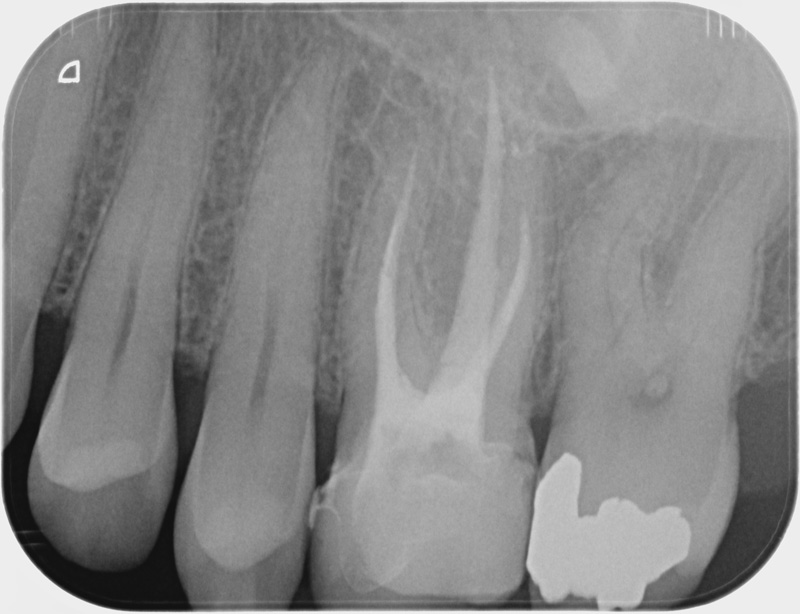

• Reprise de traitement endodontique : La manœuvre consiste à retourner à l’intérieur des racines d’une dent déjà traitée. Il arrive occasionnellement qu’une nouvelle inflammation se déclare suite à une reprise de carie ou une fracture de la dent, ou si le premier traitement endodontique est incomplet. Après s’être assuré que la dent lésée était conservable, il convient de désinfecter de nouveau le réseau canalaire parfois très complexe. La nouvelle obturation des canaux devra être protégée aussi rapidement que possible pour éviter une éventuelle contamination bactérienne.

Après